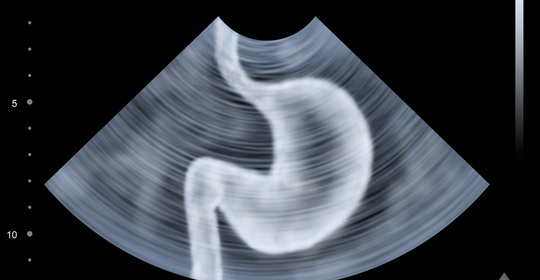

Diagnosis of Gastric Cancer

Gastric cancer is generally diagnosed through routine examinations. Commonly used methods include upper gastrointestinal endoscopy. The endoscope is inserted through the mouth and down the throat into the esophagus to examine the esophagus, stomach, and duodenum for abnormal areas. If gastric cancer is detected during the examination, further tests such as CT scans may be performed to more accurately identify the cancer.